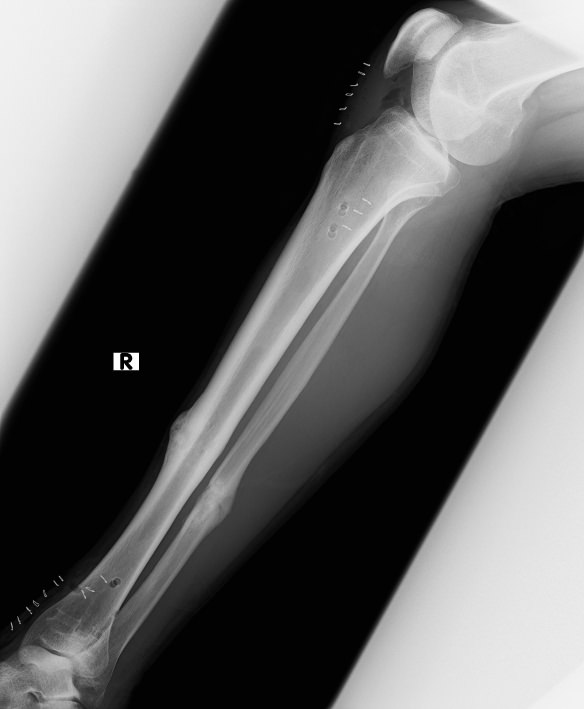

下は抜釘直後の横から見たレントゲン。膝下付近と足首付近にぽっかり穴があいてるのが確認できると思います。これがネジの入ってた場所(白く並んでる小さなのは傷口を留めるホッチキスみたいなもの)